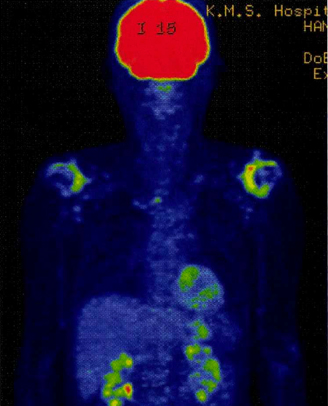

- 造影後T1強調像

大転子、小転子、坐骨結節、棘突起に造影効果

- 【反応性関節炎 reactive arthritis(ReA)】

泌尿器や腸管等の関節以外の部位の細菌感染症後に起こる関節炎である。

Chlamydia、Salmonella、Shigella、Yersinia、Campylobacterなどの感染が契機となる。

腱や靱帯,関節包が骨に付着する部位である付着部(enthesis)に炎症が起きやすいという興味深い特徴がある。